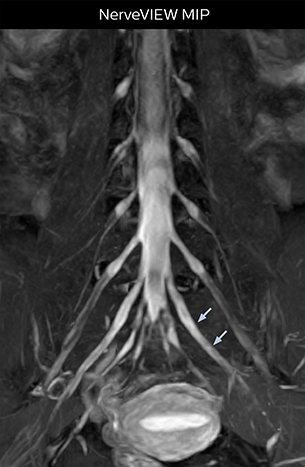

Northern Fukushima Medical Center (NFMC) Imaging Center uses the 3D NerveVIEW sequence for performing MR neurography, particularly in patients with pain and weakness in the lower limb. “It is included in about 20% of the approximately 150 lumbar spine MRI exams each month at NFMC, and can help us to determine if structures are impinging on the nerves,” says Hajime Tanji, RT, MRI technologist at NFMC.

“In such case, we would then browse through axial T2-weighted MR images slice by slice and mentally reconstruct the actual situation based on both radiculography and MRI. Fortunately, NerveVIEW can now very well show nerve courses and presence of nerve compression or edema in one single image series.” “We have often seen NerveVIEW directly depict details of the nerve compression that were not observed by radiculography. Therefore, we think that with NerveVIEW we can reduce the number of invasive examinations, especially for some patients with lumbar plexus symptoms.”

The key concept in MR neurography, Dr. Yabuki stresses, is the ability to directly visualize spinal nerves, versus inferring the presence of pathology indirectly. “Before NerveVIEW, we estimated compression of the nerve by looking for the presence or absence of fat signal on other MR images,” he says.

“For example, in sagittal images, when the presence of fat is observed in the intervertebral foramen, it suggests that there is a margin around the nerve. Similarly, the absence of fat indicates that the nerve is being compressed. So, we used to deduce nerve compression indirectly. With NerveVIEW, however, we can observe the condition of the nerves directly, regardless of the presence or absence of fat. We always prefer such direct observation of anatomy over having to make an inference about it.”

“The intra-luminal signal of veins, especially around the intervertebral space, can be suppressed well with NerveVIEW. As a result, we can easily observe the detailed nerve structure around the posterior ganglion,” he says. “This is why we use 3D NerveVIEW for intraforaminal stenosis and extraforaminal stenosis/herniation (lateral disc herniation). On the other hand, if herniation is suspected to exist inside the dorsal root ganglion (DRG), balanced TFE or ProSet-FFE is applied. NerveVIEW is not suitable for evaluating the median type of herniation.” The SE-EPI DWI-based method for MR neurography works well for large FOV exams like whole-body MRI, but focal examination of nerves is often limited by the attainable spatial resolution (both inplane and slice direction) and geometric distortion. “3D NerveVIEW achieves higher in-plane resolution – close to our other routine spine sequences – and the source images can be used instead of adding a fat-suppressed T2-weighted sequence,” Tanji says.

According to Tanji, methods such as ProSet FFE, STIR or 3D VISTA are anatomically nonselective because background signals, for instance from blood vessels, often interfere with nerves, which hampers evaluation of details, especially at the peripheral side of the nerves.

“Recently, the two surgical methods extreme and oblique lateral interbody fusion (XLIF and OLIF) have become mainstream for minimally invasive treatment of lumbar spinal canal stenosis and intervertebral foramen stenosis. With these surgical techniques, the spine is approached from the flank, and prior knowledge of the exact anatomy of the lumbosacral plexus would be extremely helpful. To that end, high slice resolution (less than 1 mm acquisition) that enables sharper sagittal MPR images will be needed.”

“For both brachial and lumbar plexus, we are currently using a 230 mm FOV and voxels of about 1 x 1 x 2 mm acquired (1 x 1 x 1 mm reconstructed). This provides us a good representation of the nerves, even though this FOV is relatively small. Regarding the inplane resolution, we hope to be able to bring that down to 0.7 mm, similar to our typical 2D multislice T2W images,” says Tanji.

“NerveVIEW can clearly show nerve courses and presence of nerve compression. However, when multiple abnormalities are seen, it can still be hard to determine which nerve is causing the symptoms,” says Dr. Yabuki. “In our experience so far, we see abnormal findings on NerveVIEW in about 70% of elderly patients. As the pain is usually caused by only one nerve, we thus need to find the exact corresponding nerve.” “With a nerve root block, the patient's pain is improved by infiltration of local anesthesia directly around the nerve root considered to be responsible. Knowing such nerve root block findings prior to image interpretation, helps to easily recognize abnormal findings on NerveVIEW as well. In other words, without a priori knowledge, based on symptoms and/or nerve root block findings, we must be aware of the possibility of overdiagnosis.”